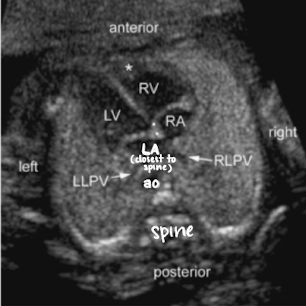

US evaluation of 4-chamber heart

make note of right and left side

lung should be seen on both sides of the heart

ensure no fluid or masses seen adjacent to/around the heart

LA is closest to AO and spine

foramen ovale opens between RA and LA

note symmetry between atria and ventricles

tricuspid valve is on right side (b/w RA and RV)

bicuspid/mitral valve is on left side (b/w LA and LV)